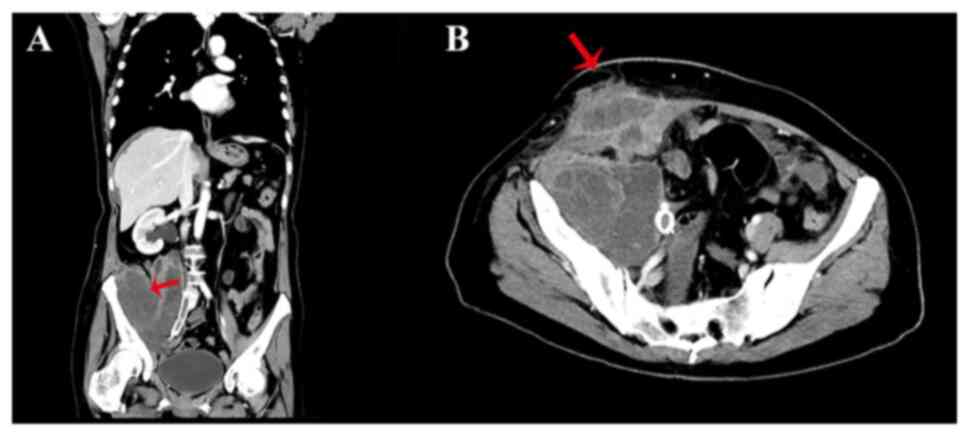

Figure 2.

Representative CT scan of the abdomen and pelvis. (A) Coronal CT scan for multiple metastases within the pelvic cavity and abdominal cavity (arrow). (B) Horizontal CT scan for rupturing of metastases (arrow). CT, computed tomography.

By August, the patient had lost ~4.6 kg, which represented a loss of 5–7.5% of total body weight occurring in <2 months, and they now returned to the hospital due to the spontaneous rupture of a mass in the right lower abdomen. Based on the Malnutrition Universal Screening Tool assessment (Fig. 1), the patient was considered to be at high risk of malnutrition (score 3) due to substantial weight loss and the current acute disease status, despite having a body mass index of 23.03 (10). A computed tomography scan confirmed that the primary cervical cancer had spread to the right lower abdomen and broken through the skin (Fig. 2). The wound, with significant exudate, was cleaned twice daily, and the patient continued to receive TPN due to poor oral intake. At 10 days after admission, the patient exhibited sudden cognitive impairment, especially in recent and immediate memory. An examination performed by a neurologist showed that she was conscious but disoriented with regard to time, place and person. The Mini-Mental State Exam (MMSE) and Montreal Cognitive Assessment (MoCA) scores were 19/30 and 17/30, respectively (11,12). In addition, ophthalmoplegia with bilateral sustained nystagmus was observed. Eye movement was normal to the left side, but abnormal to the right side. The patient could not walk due to cancer metastases within the right iliopsoas muscle and iliac wing. Consequently, a gait assessment was not performed. Mild upper-limb ataxia was observed and tendon reflexes exhibited a slight response. All other neurological examinations, including assessments of muscle tone and strength, were normal. Brain MRI and magnetic resonance angiography (MRA) were performed immediately. The MRA demonstrated normal blood vessels without restricted diffusion, which excluded the possibility of ischemic or hemorrhagic stroke. No significant abnormalities were detected on T1-weighted imaging and diffusion-weighted imaging, which further ruled out the possibility of brain metastases. However, brain MRI demonstrated hyperintensity in the periaqueductal midbrain on T2 fluid-attenuated inversion recovery imaging (Fig. 3). The patient's laboratory results were as follows: White blood cell count, 6.34×109/l (normal range, 3.5–9.5×109/l); red blood cell count, 3.69×1012/l (normal range, 4.3–5.8×10¹2/l); hemoglobin, 86 g/l (normal range, 120–160 g/l); platelets, 277×109/l (normal range, 125–350×109/l); alanine aminotransferase, 14.4 U/l (normal range, 7–40 U/l); aspartate aminotransferase, 15.9 U/l (normal range, 13–35 U/l); serum albumin, 32.62 g/dl (normal range, 40–55 g/l); potassium, 4.88 mmol/l (normal range, 3.5–5.3 mmol/l); magnesium, 0.90 mmol/l (normal range, 0.77–1.03 mmol/l); folate, 5.3 ng/ml (normal range, 3.38–5.38 ng/ml); and vitamin b12, 605 pg/ml (normal range, 211–911 pg/ml). Serum thiamine levels were not tested due to laboratory constraints. Several other conditions, including brain metastases, acute cerebrovascular disease and electrolyte imbalance, were considered and excluded based on clinical symptoms, imaging examination and laboratory results. Furthermore, the TPN regimen did not include routine thiamine supplementation, which may have promoted the development of WE. Thiamine (100 mg) was immediately administered intramuscularly three times a day. After 1 week of treatment, the patient's eye movement disorder and recent memory improved, with the MMSE and MoCA scores changing to 23/30 and 20/30, respectively. The patient was subsequently discharged and returned to her hometown. After 3 months, a telephone follow-up was conducted. It was noted that the patient showed rapid progression of the primary tumor, along with ongoing partial recent memory impairment and spatial disorientation. Ultimately, the patient passed away due to complications related to the tumor. The timeline of the disease course is presented in Fig. 4.